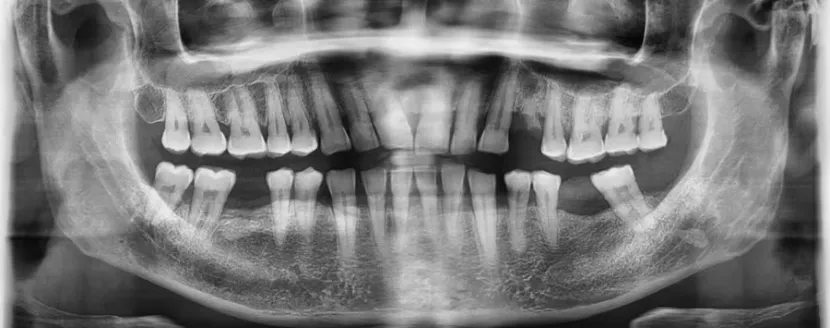

La ortodoncia interceptiva es una especialidad clave dentro de la odontopediatría, diseñada para corregir problemas dentales y de crecimiento maxilar en niños desde edades tempranas. Su principal ventaja es que actúa antes de que los problemas se agraven, evitando tratamientos más invasivos y costosos en el futuro.

El precio de la ortodoncia interceptiva en Perú varía según el tipo de aparato, la complejidad del caso y la clínica donde se realice el tratamiento.

Estos costos incluyen el diagnóstico, planificación, aparatos ortodónticos (removibles o fijos) y controles periódicos.